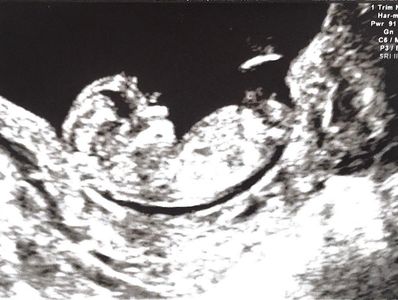

First Trimester Assessment

• Between 12+0-13+6 weeks’ gestation, estimated from your last menstrual period (LMP) or a prior ultrasound scan.

• ·Confirm fetal viability and provide an accurate estimate of the date of delivery (EDD) based on the length of the baby (crown-rump length), except in IVF pregnancies, where the gestation may already be known. Accurate dating of the pregnancy is important in assessing the growth of the baby and ensuring the optimal time of birth. Although at this gestation, the majority of pregnancies are viable, sadly, a small number may result in “silent” early pregnancy loss, which may be apparent at this scan.

• Screening for major fetal structural abnormalities. The majority of pregnancies will be developing normally. This scan aims to exclude major fetal structural defects, and although some can be diagnosed at this gestation, we also advise a detailed anatomy scan at 20-weeks.